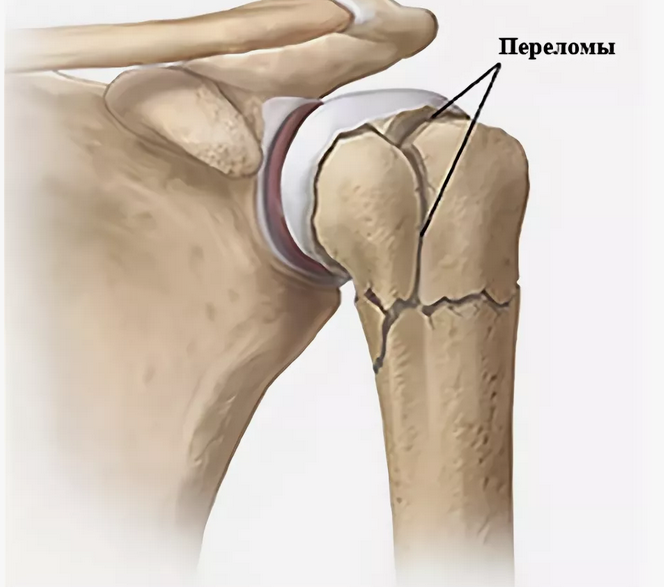

В случае перелома шейки бедра компания МосРентген Центр госпитализирует в Склиф для эндопротезирования.